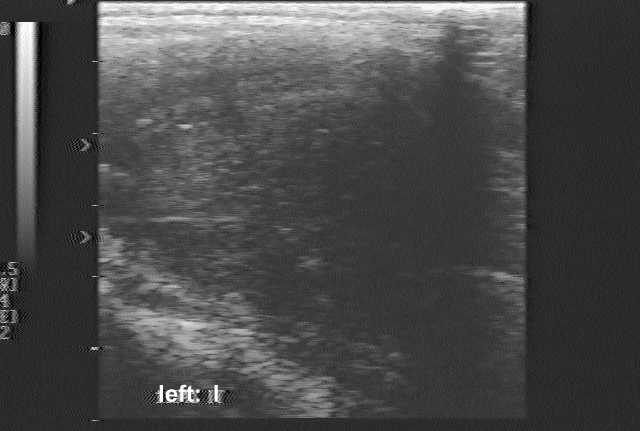

Ultrasonography: demonstrated a greatly enlarged hypoechogenic thyroid spreading retrotracheal and substernal. The vascularization was absent.